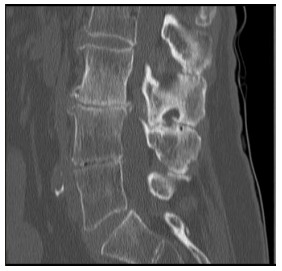

O corte tomográfico sagital da coluna lombar abaixo ilustra claramente alterações que possibilitam alguns diagnósticos, dentre os quais podemos citar: